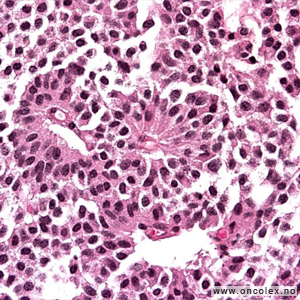

Analyse av celle- og vevsprøver

Celle- og vevsprøver sendes til cytologisk eller histologisk analyse. I tillegg til at man studerer cellene i mikroskopet, gjør man avanserte immunhistokjemiske og genetiske analyser. Nøyaktig hvilke analyser som gjøres er avhengig av hvilken type svulst man mistenker at pasienten har.